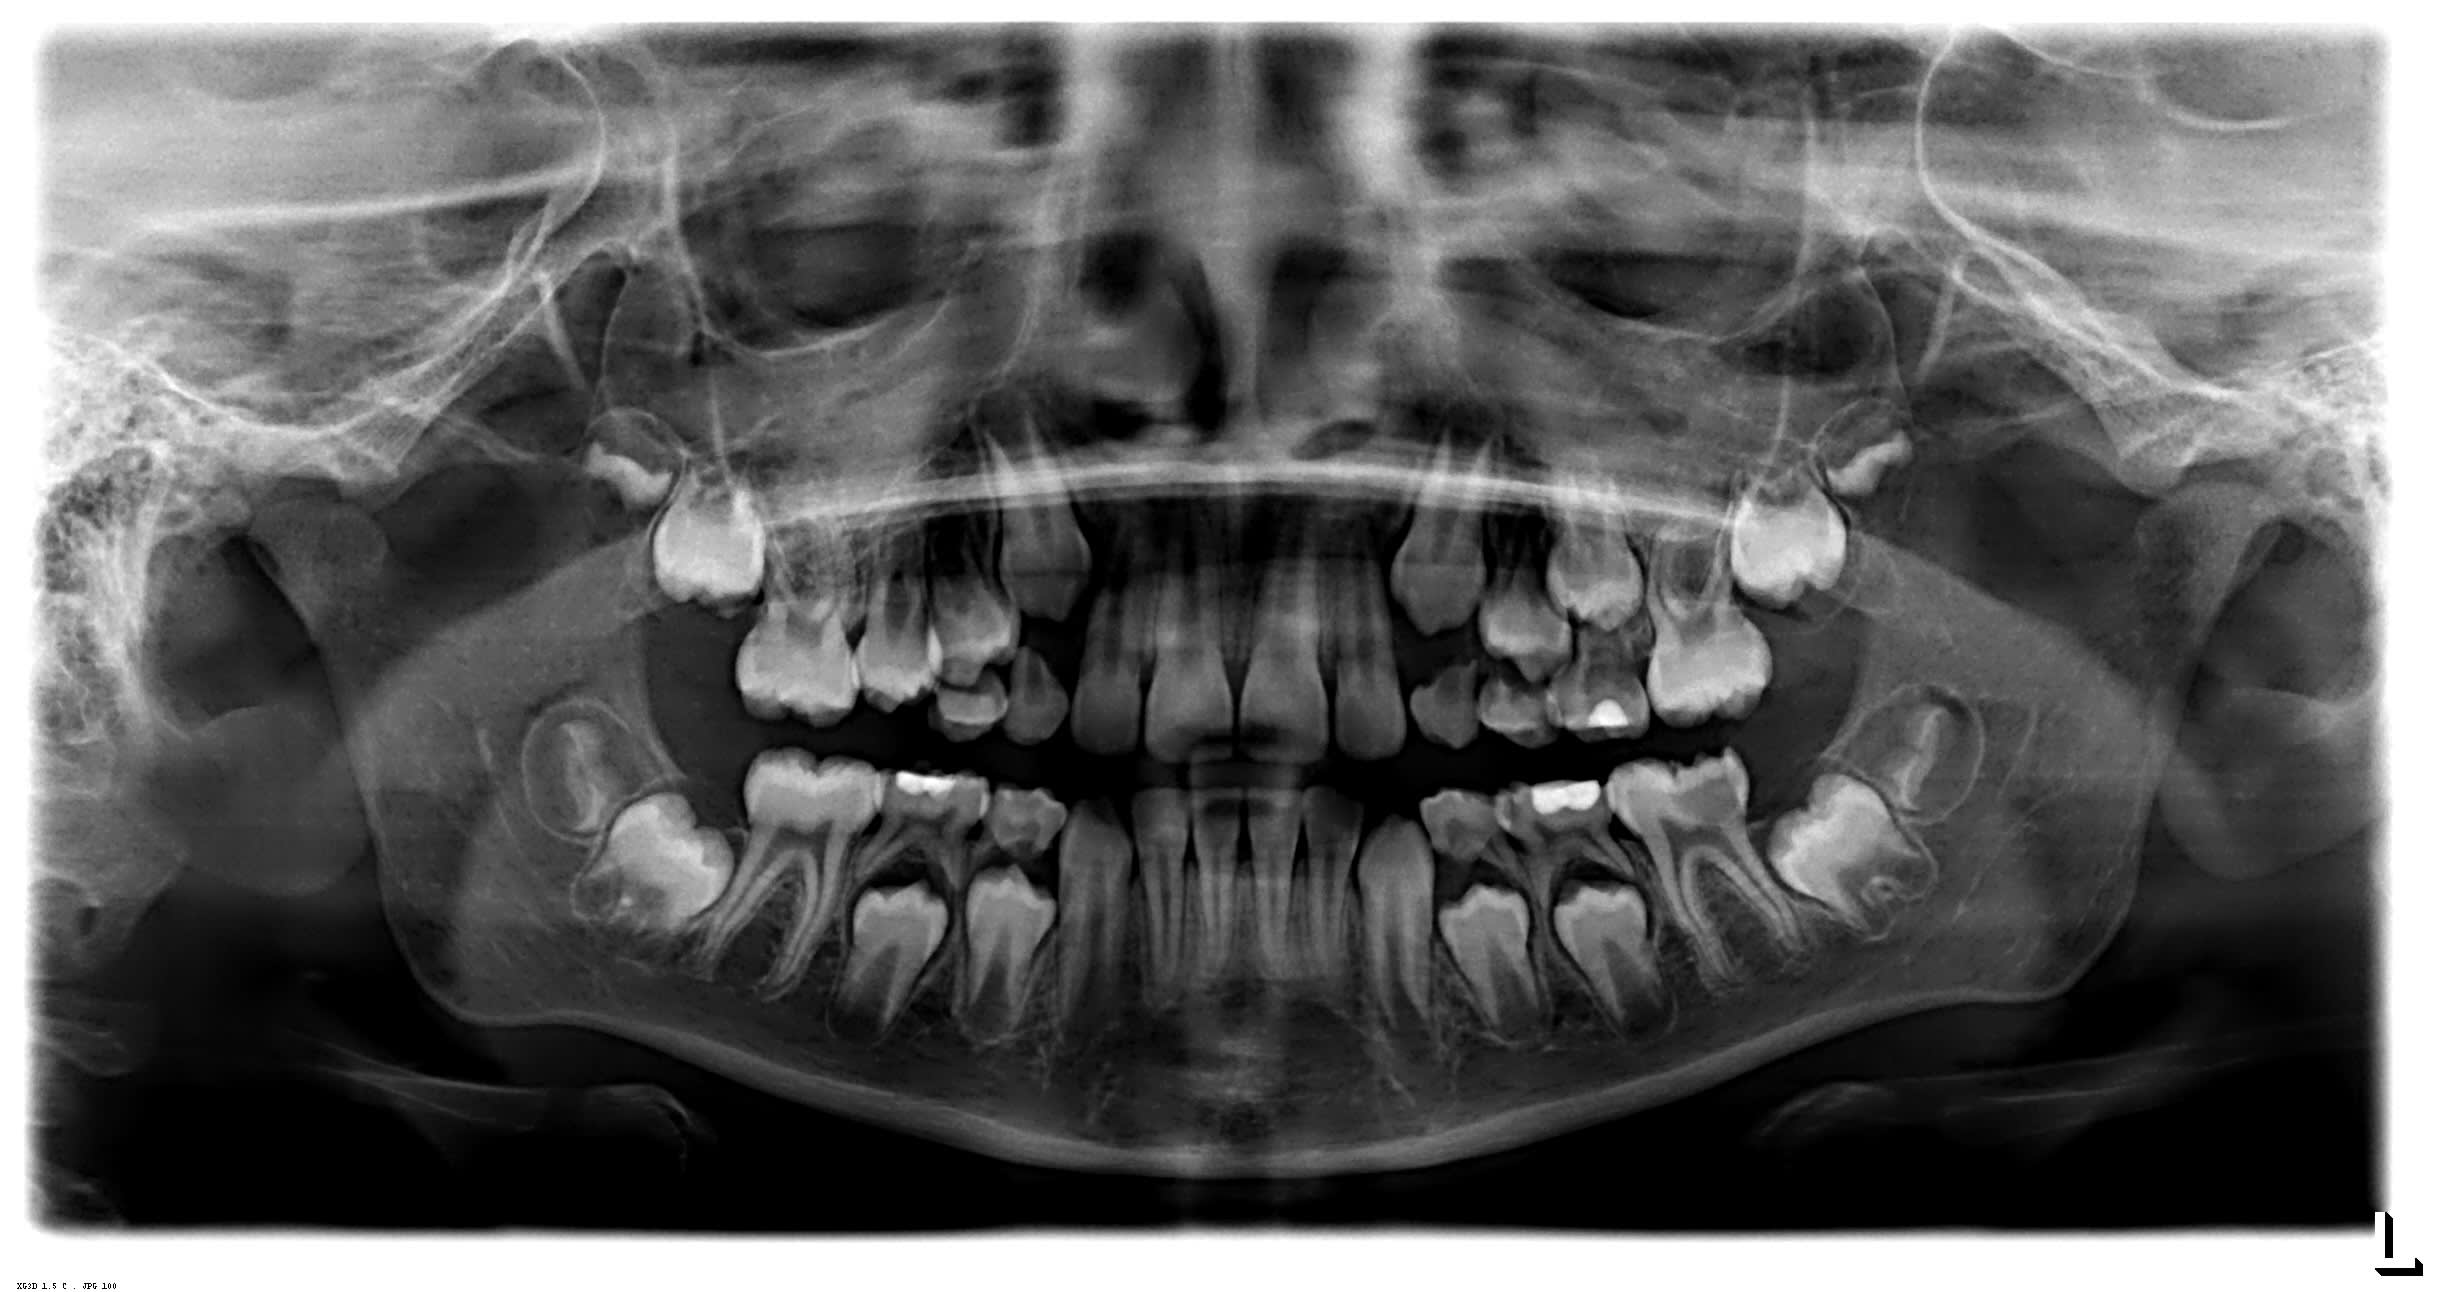

Je vais peut être devoir faire une endo de 36 sur ce patient de 9 ans. Que me conseiller vous si la carie atteint la pulpe...,si je me souviens bien les apex se ferme 6 ans après l'éruption donc vers 12 ans...

une carie comme ca a cet age la , sans retouver les mêmes sur les autres dents de 6 ans ca doit être une amélogenese incomplete

quelle que soit la solution conservatoire retenue , elle n'est pas envisageable sans un reconsitution prothétique compte tenu de la nature de l'émail résiduel et de la minceur des pans résiduels dentinaires.